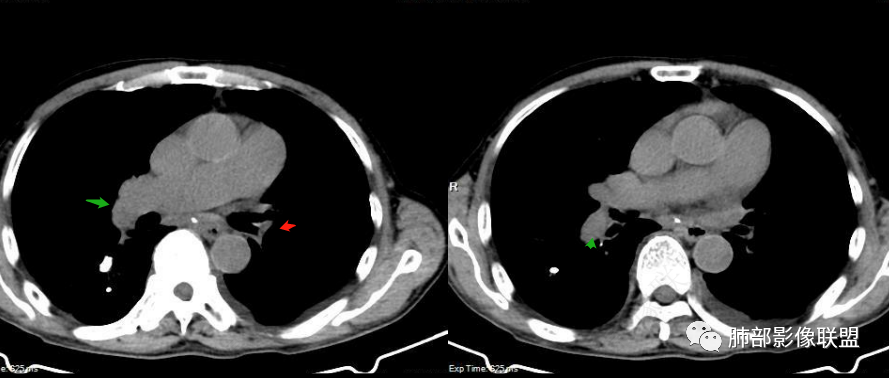

嘻嘻:2022.1.11号肺窗及增强

6.心脏影增大,右房室增大为主。(增强:左心房及肺静脉入口见充盈缺损)

7.肺动脉主干扩张,左侧肺动脉主干见混杂密度影,上下肺动脉似不能连续追踪。

(增强:左肺动脉充盈缺损、闭塞)

2.影像右侧肺水肿提示左心回流障碍。左心房及肺静脉入口见充盈缺损提示血栓存在。

3.影像胸壁迂曲扩张静脉血管提示右心回流障碍(可呼应双下肢浮肿)。

5.影像左肺动脉栓塞、闭塞——上下肺动脉以远相对纤细——左肺动脉“断供”,且存在支气管动脉扩张可能。

1.肺栓塞的CT表现

(1)肺缺血:当肺叶或肺段动脉栓塞时,相应区域内的肺血管影纤细或减少,肺野密度减低。部分患者肺体积缩小。

(2)“马赛克”征:肺内灌注不均匀,表现为正常的肺组织代偿性高灌注与栓塞所致相应肺组织灌注下降相间存在。

(3)肺动脉主干异常:双侧多于单侧,右肺多于左肺,下肺多于上肺,较大肺动脉栓塞可显示为肺动脉主干及分支内异常密度灶,新鲜血栓多表现为高密度,陈旧性血栓多表现为低密度或钙化等。病变的肺动脉因较大血栓嵌顿而增粗,其远端血管因血流减少而变细。

(4)心影增大,以右心室增大为主,伴有肺动脉高压。